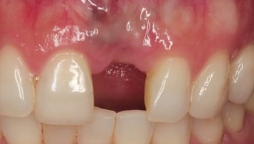

CLINICAL VIDEO NARRATED Immediate Tooth Replacement with Simultaneous Socket and

CAT# CV-095-L

NARRATED Immediate Tooth Replacement with Simultaneous Socket and Soft Tissue Graft with Narration

Dr. Sascha A. Jovanovic

CLINICAL VIDEO Immediate Tooth Replacement with Simultaneous Socket and Soft Tis

CAT# CV-095

Immediate Tooth Replacement with Simultaneous Socket and Soft Tissue Graft

CLINICAL VIDEO Immediate Tooth Replacement of Failing Tooth #11

CAT# CV-067

Immediate Tooth Replacement of Failing Tooth #11